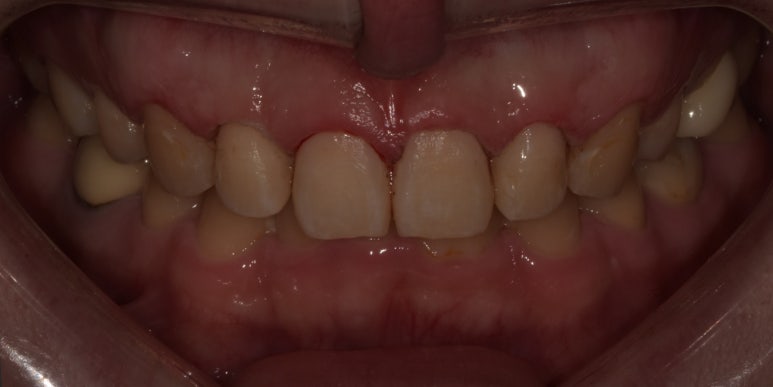

잇몸성형 전후 사진

(전) 2023-05-13 (후) 2023-05-26

위 환자분은 잇몸라인이 다소 평평해보여 라운드하고 고른 라인을 만드는데 중점을 두었습니다.